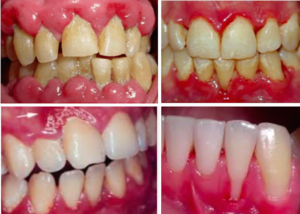

A periodontite agressiva juvenil é uma doença gengival séria que afeta jovens. Ela causa destruição rápida do osso e dos tecidos que sustentam os dentes. O diagnóstico precoce é crucial para evitar a perda dentária.

Vamos direto ao ponto sobre como tratar a periodontite agressiva juvenil. O primeiro passo é crucial: um diagnóstico rápido e preciso. Não dá para brincar com isso, sabe? Um dentista experiente vai ser capaz de identificar os sinais logo de cara. Ele vai olhar para as gengivas, verificar a perda óssea e avaliar a velocidade com que isso acontece. Isso é fundamental porque a periodontite agressiva juvenil tem suas particularidades e precisa de uma abordagem específica.

Entender a causa raiz é parte desse diagnóstico. Às vezes, fatores genéticos podem estar envolvidos, e isso a gente não controla. Mas outras vezes, o acúmulo de placa bacteriana e a dificuldade em fazer a higiene correta acabam contribuindo. O dentista vai investigar tudo isso com exames clínicos e, se necessário, radiografias. Ele vai querer saber o histórico familiar, seus hábitos de higiene e se você tem alguma condição de saúde que possa influenciar.

A periodontite agressiva juvenil, quando não tratada, pode trazer sérias consequências para a saúde bucal. Por isso, a limpeza profissional não é só um cuidado estético, é a base para o controle dessa condição. Dentistas e higienistas têm as ferramentas e o conhecimento para remover aquela placa bacteriana e o tártaro que o dia a dia em casa não alcança. É um passo fundamental para frear a progressão da doença.

Nesse tratamento, o foco é a remoção minuciosa das bactérias. Os profissionais utilizam instrumentos específicos para limpar profundamente as bolsas periodontais, que são aquelas espaços que se formam entre o dente e a gengiva quando a doença avança. O objetivo é criar um ambiente bucal mais saudável, onde a gengiva possa começar a se recuperar e a inflamação diminua. É um trabalho delicado, que exige precisão.

Gengivas que sangram facilmente, inchaço e vermelhidão são os primeiros alertas. Mau hálito persistente também pode indicar algo. Observe o sorriso do seu filho atentamente.